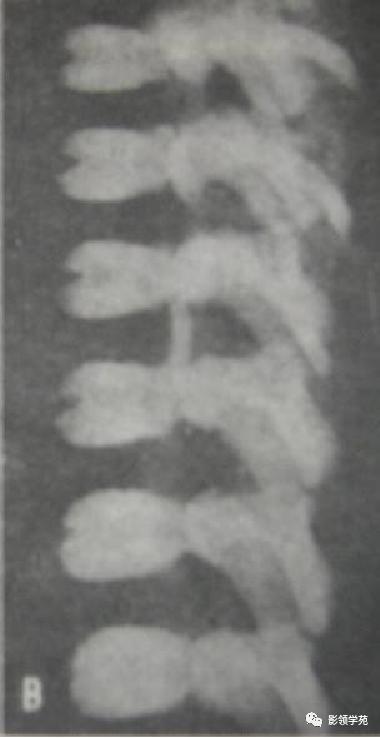

永存性骨骺

又称生理性骨块分离、椎缘骨、锥角离断体边缘骨等。在骨的生长发育过程中,当骺板发育到成熟阶段,其软骨的增殖和成骨活动停止,骺板因某些因素未被骨化,使骨干与干骺端融合障碍而形成。